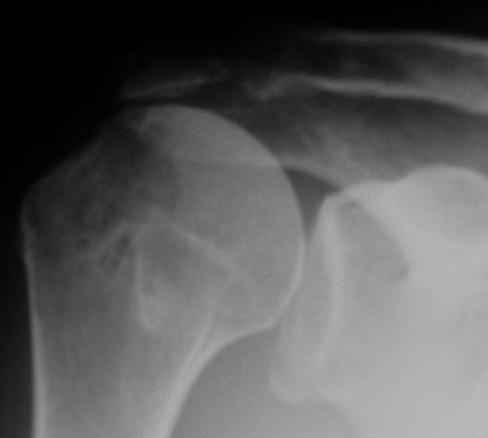

Физический активный мужчина 50 лет в мае 2009 года был оперирован на правом плечевом суставе. Выполнялся открытый шов надостной мышцы и субакромиальная декомпрессия по поводу ее частичного разрыва и импиджмент синдрома III степени. Послеоперационный период протекал без осложнений. Гипсовая иммобилизация в положении отведения плеча до 45 градусов в течение 6 недель.В последующем, несмотря на активные занатия ЛФК, сформировалась приводяще-внутриротационная контрактура оперированного сустава (отведение до 80 градусов, наружная ротация до 15 градусов. Болевого синдрома нет, при пассивном отведении плеча создается впечатление "механического" препятствия движению.На контрольных рентгенограммах складывается впечатление о сформировавшемсся верхнем подвивихе головки правой плечевой кости, как о причине контрактуры. Хотелось бы услышать мнение коллег о такттике дальнейшего лечения.

Верхний подвывих в такой ситуации может быть проявлением ротаторной артропатии, как следствия более массивного, чем частичный разрыв сухожилия надостной мыщцы, повреждения вращательной манжеты. И значит нужно думать о том, насколько полно восстановлена манжета, адекватно ли был расценен объем ее повреждения. Что за шов применялся? Якорных винтов не видно. И почему гипсовая иммобилизация? Есть прекрасные надувные отводящие подушки, позволяющие ранние движения.

В качестве примера - снимки до и после восстановления целостности вращательной манжеты после 3-хмесячной давности полного разрыва. Видно, что верхний подвывих устранен.